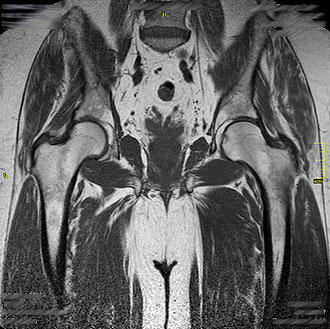

Die MRT Hüfte liefert wertvolle Informationen bei Schmerzen, Bewegungseinschränkungen oder nach Operationen.

Sie zeigt Hüftdysplasien, Entzündungen, Hüftkopfnekrosen, Impingementsyndrome, Zustände nach Endoprothesen sowie Schleimbeutelentzündungen (Bursitis).

Im Kernspin Zentrum Köln werden spezielle MRT-Sequenzen verwendet, um auch frühe Veränderungen sichtbar zu machen.